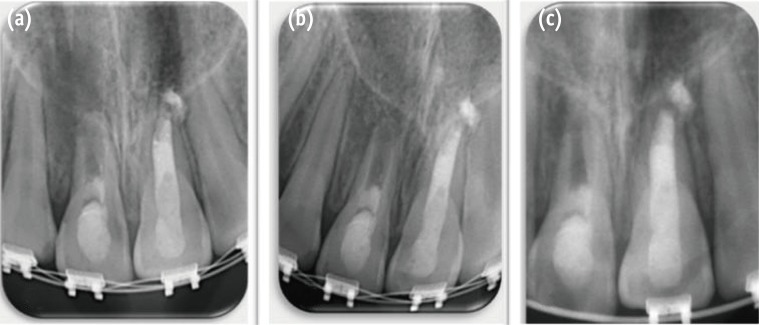

The treatment options were discussed with the patient's mother. It was decided that the patient would benefit from another revascularization procedure rather than regular apexification or an apical plug. A consent form was signed after approval of the proposed protocol to initiate revascularization treatment. A rubber dam was applied, and the tooth was accessed following local anesthesia (1.8 mL of 2% lidocaine with 1:100,000 epinephrine) administration using a dental operating microscope (Global Surgical Corp., St. Louis, MO, USA). The MTA root canal filling was removed with CPR ultrasonic tips (Obtura Spartan Endodontics, Algonquin, IL, USA) set at low power. The vibration of the CPR ultrasonic tips caused the MTA filling materials to break up into pieces, and then the canal was flushed with saline to remove root canal filling debris, irrigated with 20 mL of 5.25% sodium hypochlorite (Henry Schein, Melville, NY, USA), and then rinsed with sterile saline solution. The pulp chamber was carefully dried with paper points and filled with double antibiotic paste (DAP) consisting of a mixture of ciprofloxacin (Ciprobay, Bayer Pharma, Leverkusen, Germany) and metronidazole (Flagyl, Sanofi Aventis, Frankfurt, Germany) in a 1:1 ratio prepared with saline (wt/vol 2.5:1) using a lentulo spiral (Dentsply, Maillefer, Ballaigues, Switzerland). Access was sealed with temporary filling material (Cavit, 3M ESPE, St. Paul, MN, USA), and a radiograph was taken (Figure 2).

Figure 2

Periapical radiograph after placement of double antibiotic paste (DAP).

Figure 2 Periapical radiograph after placement of double antibiotic paste (DAP).